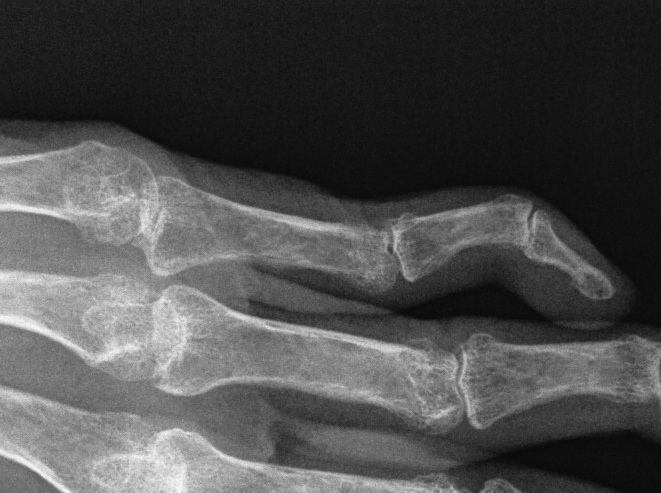

PIPJ flexed / DIPJ hyperextended / MCPJ hyperextended

2. Lateral bands displace volar

3. DIPJ hyperextends secondary to PIPJ flexion

- contracted oblique retinacular ligament

- becomes fixed

- examination finds limited DIPJ flexion with PIPJ in extended position